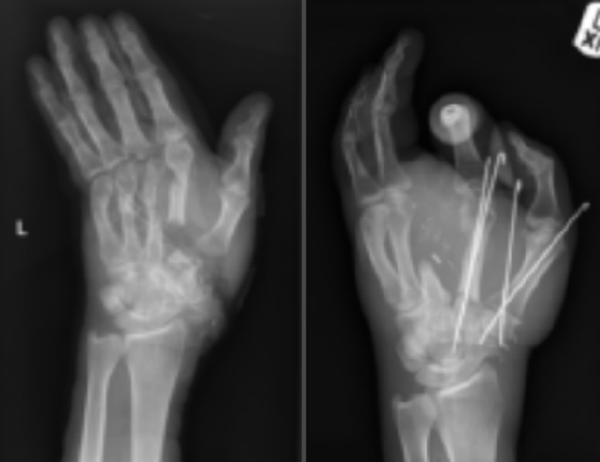

It would take surgeons some 17 hours to repair the damage, which saw the surgical team fixing Lelliott’s broken bones, establishing a good blood and nerve supply to his fingers and finding a way to reconstruct the dying skin missing from his palm.

"We had to join not just tendons and nerves and arteries, but put in grafts for every single piece of tissue that we needed to repair,” Roger Adlard, a consultant plastic surgeon involved in Lelliott’s procedure, told the BBC.

"It had been described as a sub-total hand amputation, which was true. However, it had been cut off almost completely in two places - at the base of his palm and again just below the fingers - resulting in a double-level amputation.”

Adlard was aided in the hours-long operation by fellow plastic surgeon Farid Ali, who specializes in microsurgery. The pair, along with several medical officials, worked to remove veins from Lelliott’s foot and nerves from his forearm in order to continue repairing the severely mangled hand.